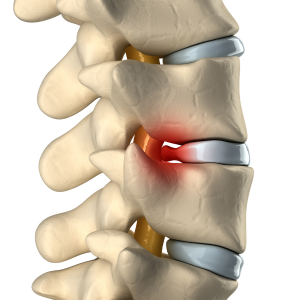

Chiropractic is a healthcare profession that focuses on the diagnosis, treatment, and prevention of disorders of the musculoskeletal system and the nervous system. Chiropractors believe that the body has the innate ability to heal itself, and they use a variety of techniques to help your body achieve this goal.

The most common chiropractic technique is spinal adjustment, which involves using gentle pressure to realign your spine. Chiropractors may also use other techniques, such as massage therapy, exercise therapy, and heat therapy.

What is a chiropractic adjustment?

A chiropractic adjustment is a procedure in which a chiropractor uses their hands or a small instrument to apply a controlled, sudden force to a spinal joint. The goal of this procedure is to improve spinal motion and improve your body’s physical function.

During a chiropractic adjustment, you will lie on a special table. The chiropractor will place their hands on your spine and use gentle pressure to realign your joints. You may hear a popping sound during the adjustment. This is normal, it is not usually painful, and is caused by the release of gases from your joints.